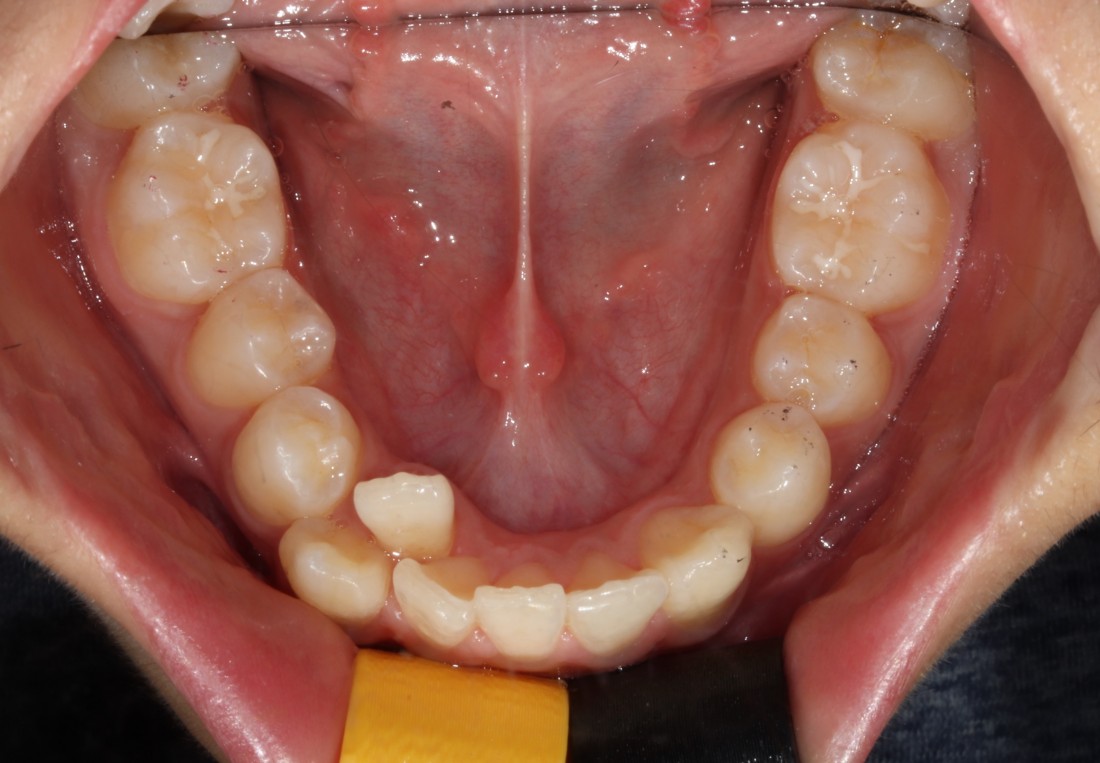

다양한 과개교합 교정 전/후 사진은

위의 사진을 클릭하시면 확인하실 수 있으며,

부정교합은 단순히 치열을 고르게 하는

치열교정과는 다르게

턱관절 건강도 따져보아야하고,

충치치료 등 필요한 진료들이

다양하게 있을 수 있기 때문입니다.